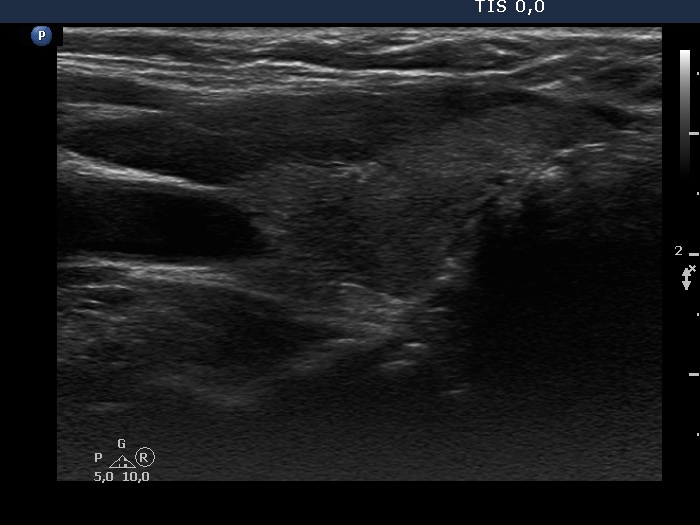

Consecutive patients with Hashimoto's thyroiditis - Case 13. (ultrasonographic picture 7)

Left lobe, longitudinal scan. This lobe also contains more hypoechogenic areas.